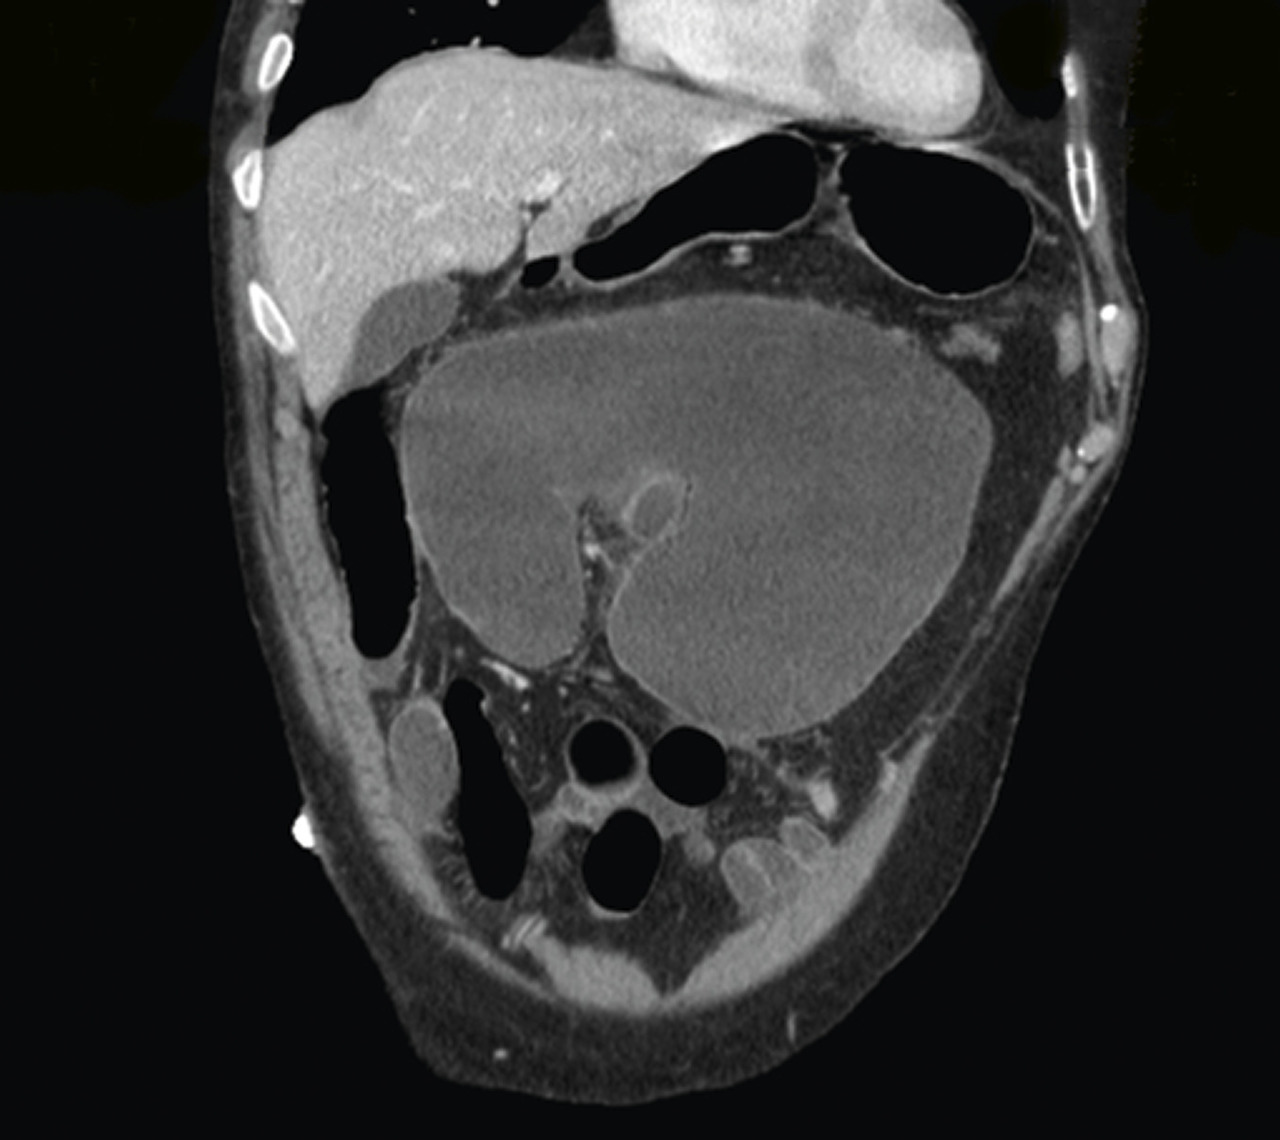

Volvulus du cæcum sur une coupe frontale de tomodensitométrie

2. Volvulus du cæcum sur une coupe frontale de tomodensitométrie